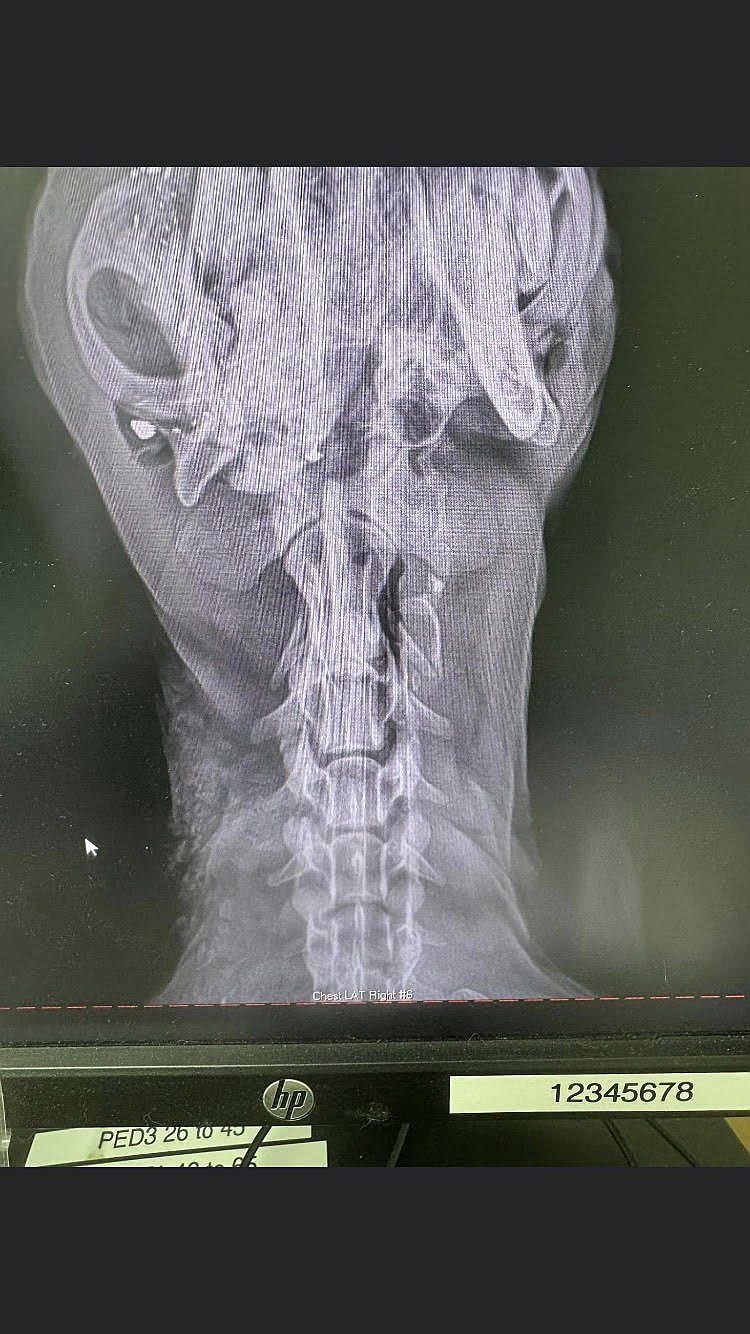

Animal Control received a report of a dog found wandering with a clear head wound from a bullet. But no one could find the dog. The cold, the snow, the misery set it. And no one could find her.

Then another call came in about the same dog in the same location. Where had she been? How had she survived? Who did this?

Thankfully, she was found and rushed to the hospital to receive treatment but she has a journey to go to be out of the woods.

Infection has set in and she will need surgery again very soon - and will likely lose teeth. She remains sweet and kind and wiggy despite her odds and we are desperate to get her in shape to be loved forever.